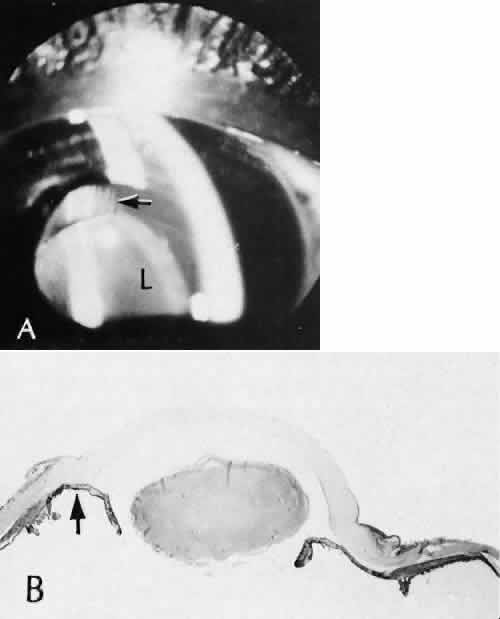

Misplacement of an anterior segment incision too far anteriorly into the cornea may create an unacceptable degree of scarring or astigmatism, whereas misplacement too far posteriorly (Fig. 25) may cause the incision to enter the ciliary body instead of the anterior chamber, an especially serious event in glaucoma filtering procedures. Misplacement oflimbal sutures (Fig. 26) may cause anterior wound gaping if placed too far posteriorly or posterior wound gaping if placed too far anteriorly. A deep suture may enter the anterior chamber and lead to wicking and a flat anterior chamber postoperatively. A suture placed at different depths in the two sides of the wound results in faulty apposition of the wound edges.

Fig. 25. The ciliary processes (arrow) in a wound placed too far posteriorly in an attempted iridencleisis (a type of glaucoma procedure). Persistent flat anterior chamber followed the formation of peripheral anterior synechiae (inset), producing secondary closed-angle glaucoma. The globe was subsequently enucleated. (Hematoxylin-eosin stain; × 28.)

Fig. 26. Complications related to a limbal wound. A. The posterior edges of the limbal wound are poorly apposed. Incarcerated vitreous can be identified in the wound at higher magnification, (inset). The cut edges of Descemet's membrane are widely displaced (d). (Hematoxylin-eosin stain; A, × 54; inset, × 101.) B. Vitreous is incarcerated into the wound immediately anterior to an area of total anterior synechiae. C. At higher magnification, vitreous can be clearly identified in the wound. A fibrous membrane is present posterior to Descemet's membrane. The arrows indicate the cut edges of Descemet's membrane. (Periodic acid/Schiff stain; B, × 16; C, × 40.)